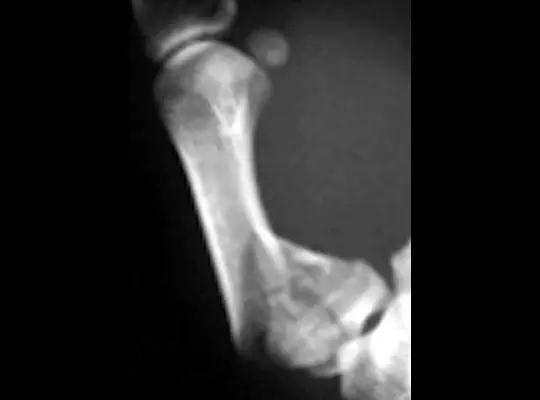

14.第五跖骨骨折

第五跖骨基底部骨折的不同类型:Stress 骨折;Jones 骨折:第五跖骨基底部以远 1 英寸内的骨折称为 Jones 骨折; Avulsion 骨折。

Jones 骨折正位片(来源:Radiopaedia)

Jones 骨折斜位片(来源:Radiopaedia)